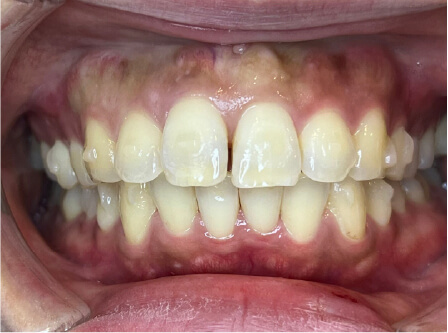

叢生の症例

41歳

女性

相談内容

横から見た時のガタガタが気になる

カウンセリング・診断結果

インビザライン、正中は上11に合わせていく、抜歯・拡大装置・IPR・アタッチメントOK

治療内容・方法

アライナー矯正

術後の経過・現在の様子

クリアライナー使用

治療のリスク

痛み・歯根吸収・歯肉退縮・虫歯・後戻り

費用・治療期間

880,000円、7ヶ月